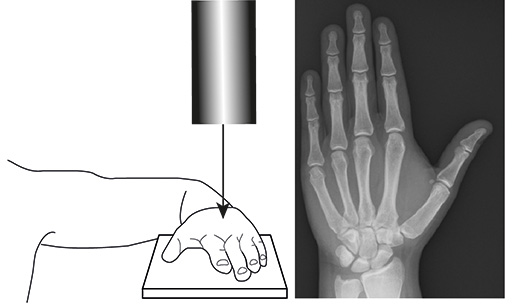

Во время рентгеновского исследования пациент садится на стул рядом с аппаратом. Для получения качественного снимка важно правильно расположить руку: она должна быть согнута в локте, а кисть лежать на столе. Пациент должен зафиксировать плечевой, локтевой и лучезапястный суставы в неподвижном состоянии на протяжении всего процесса съемки. Выбор проекции для рентгена зависит от исследуемого сустава или кости:

Прямая проекция. Кисть располагается на столе горизонтально, а рентгеновские лучи направляются перпендикулярно к кисти. Это позволяет исследовать кости запястья (трехгранную, полулунную, ладьевидную, головчатую, крючковатую, трапециевидную), состояние лучезапястного сустава, пястных костей, запястно-пястных суставов и фаланг пальцев. Однако гороховидная кость не будет видна, для ее обследования потребуется другая проекция.

Процедура проводится на специальной установке с расположением кисти на закрепленной площадке, которая и будет областью для сканирования. Остальная часть тела пациента, которая не обследуется, защищается при помощи свинцовой мембраны. В нашем центре мы проводим рентген кисти только в прямой проекции.